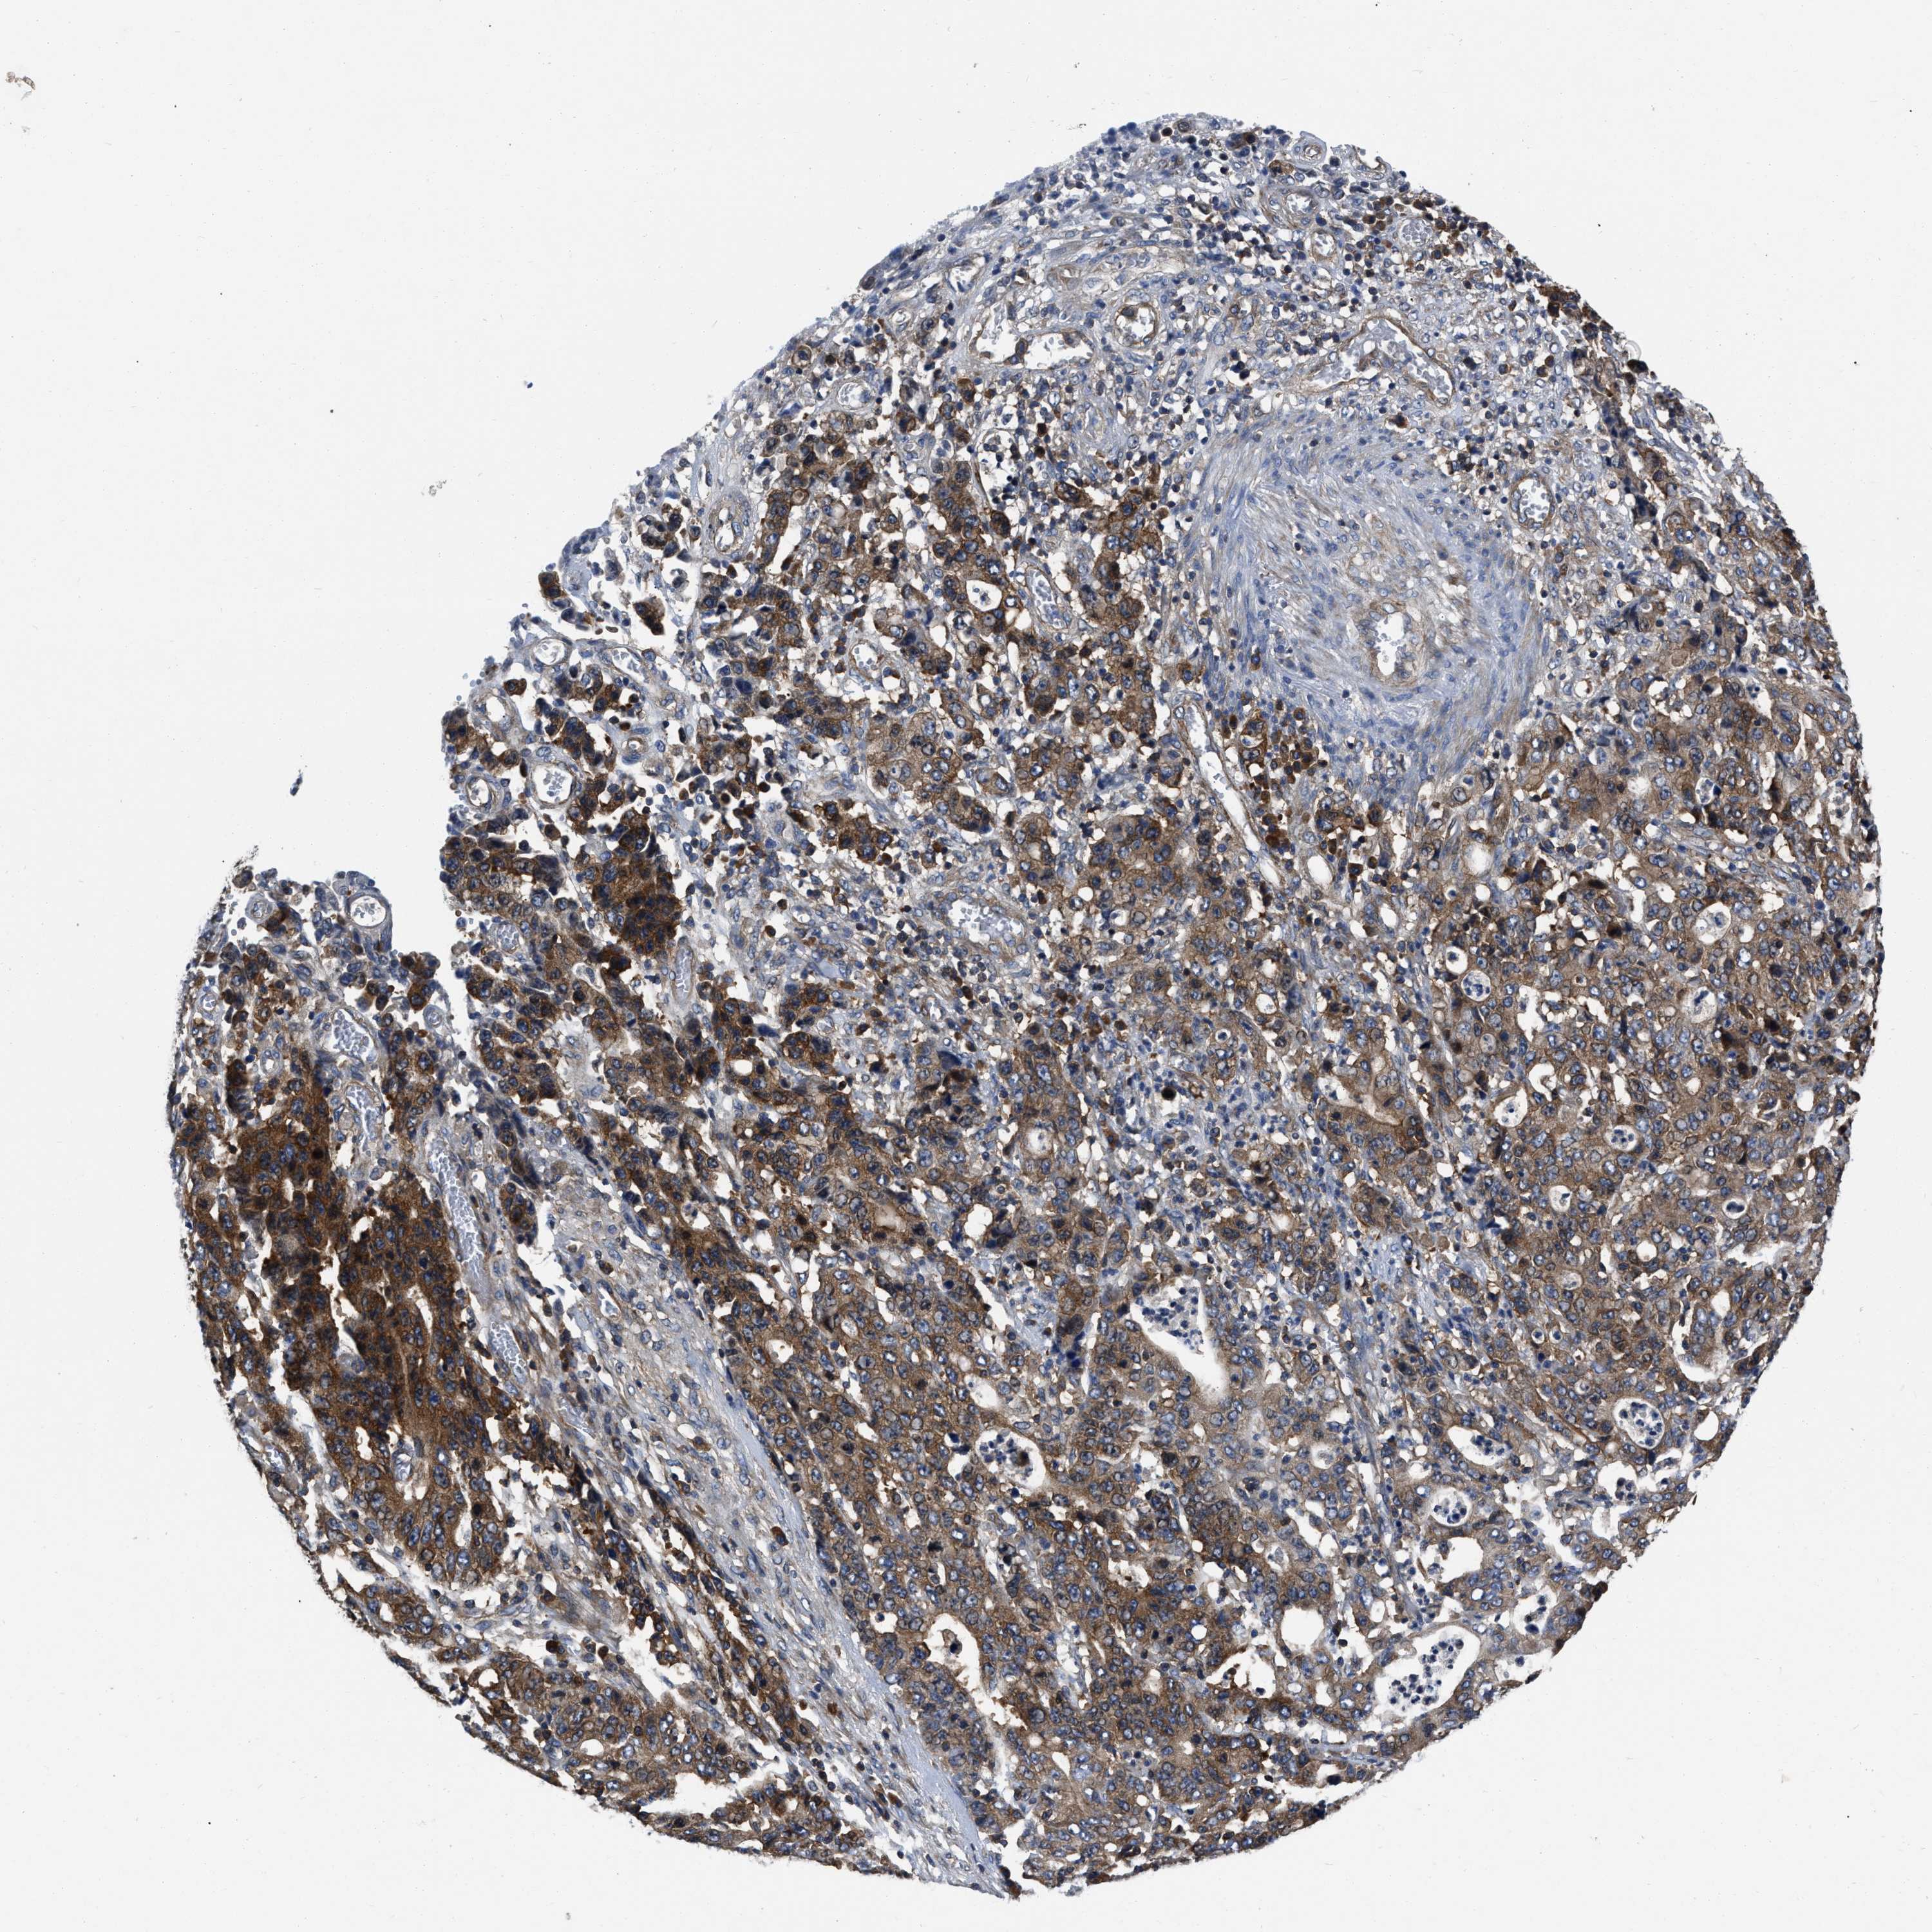

STOMACH CANCER - Protein expressioni

A mouse-over function shows sample information and annotation data. Click on an image to view it in a full screen mode. Samples can be filtered based on level of antibody staining by selecting one or several of the following categories: high, medium, low and not detected. The assay and annotation is described here.

Note that samples used for immunohistochemistry by the Human Protein Atlas do not correspond to samples in the TCGA dataset.

Antibody stainingi

Antibody staining in the annotated cell types in the current human tissue is reported as not detected, low, medium, or high, based on conventional immunohistochemistry profiling in selected tissues. This score is based on the combination of the staining intensity and fraction of stained cells.

Each image is clickable and will lead to virtual microscopy that enables deeper exploration of all samples and also displays staining intensity scores, fraction scores and subcellular localization as well as patient and tissue information for each sample.

Antibody HPA017936

Antibody HPA018950

Antibody HPA018954

Staining

High

Medium

Low

Not detected

Intensity

Strong

Moderate

Weak

Negative

Quantity

>75%

75%-25%

<25%

None

Location

Nuclear

Cytoplasmic/membranous

Cytoplasmic/membranous,nuclear

Adenocarcinoma, NOS